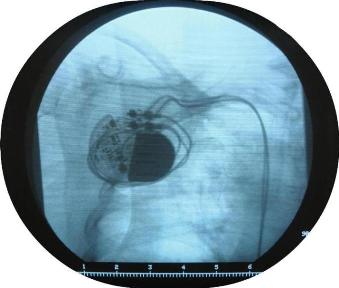

El marcapasos se implanta quirúrgicamente, por lo general, cerca de la clavícula. El dispositivo se conecta al corazón mediante dos alambres, llamados electrodos del marcapasos. Cuando la frecuencia cardiaca disminuye, se acelera o se torna irregular, el marcapasos dispara impulsos eléctricos al corazón. Esa estimulación le ayuda al corazón a latir a la velocidad o paso adecuado.

Puede requerir una estadía de 1 a 2 días para que el médico confirme que la situación del paciente es estable y que el marcapasos está en funcionamiento. A todos los pacientes se les aconseja no torcer ni manipular el marcapasos, o interferir con la cicatrización de la zona de incisión. El médico también puede realizar uno o más estudios. Una radiografía, ECG y ecocardiograma pueden ayudar a confirmar que el marcapasos y las derivaciones están en la ubicación apropiada y funcionando correctamente.